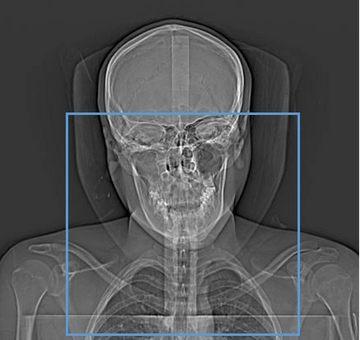

As a general rule, scan field should be from Carina to Sella turcica when patient is positioned properly. Be aware of diagnosis to ensure that all relevant anatomy is included. If patient is unable to position properly and a large portion of brain/skull will need to be scanned please clear with radiologist to ensure that no additional orders will need to be obtained

SCAN FROM AORTIC ARCH TO SELLA TURCI